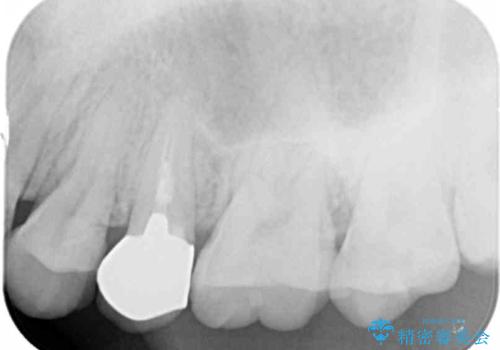

X線撮影を行い、隣接面に多発した虫歯と歯ぐきよりも深くなってしまった虫歯を小矯正をおこなったのちのセラミック治療で問題を解決します。

小矯正を行い深い虫歯を改善した後は、小手術を行うことで歯ぐき・周囲歯槽骨の状態を整えることでより安定した歯周環境を得ることができます。